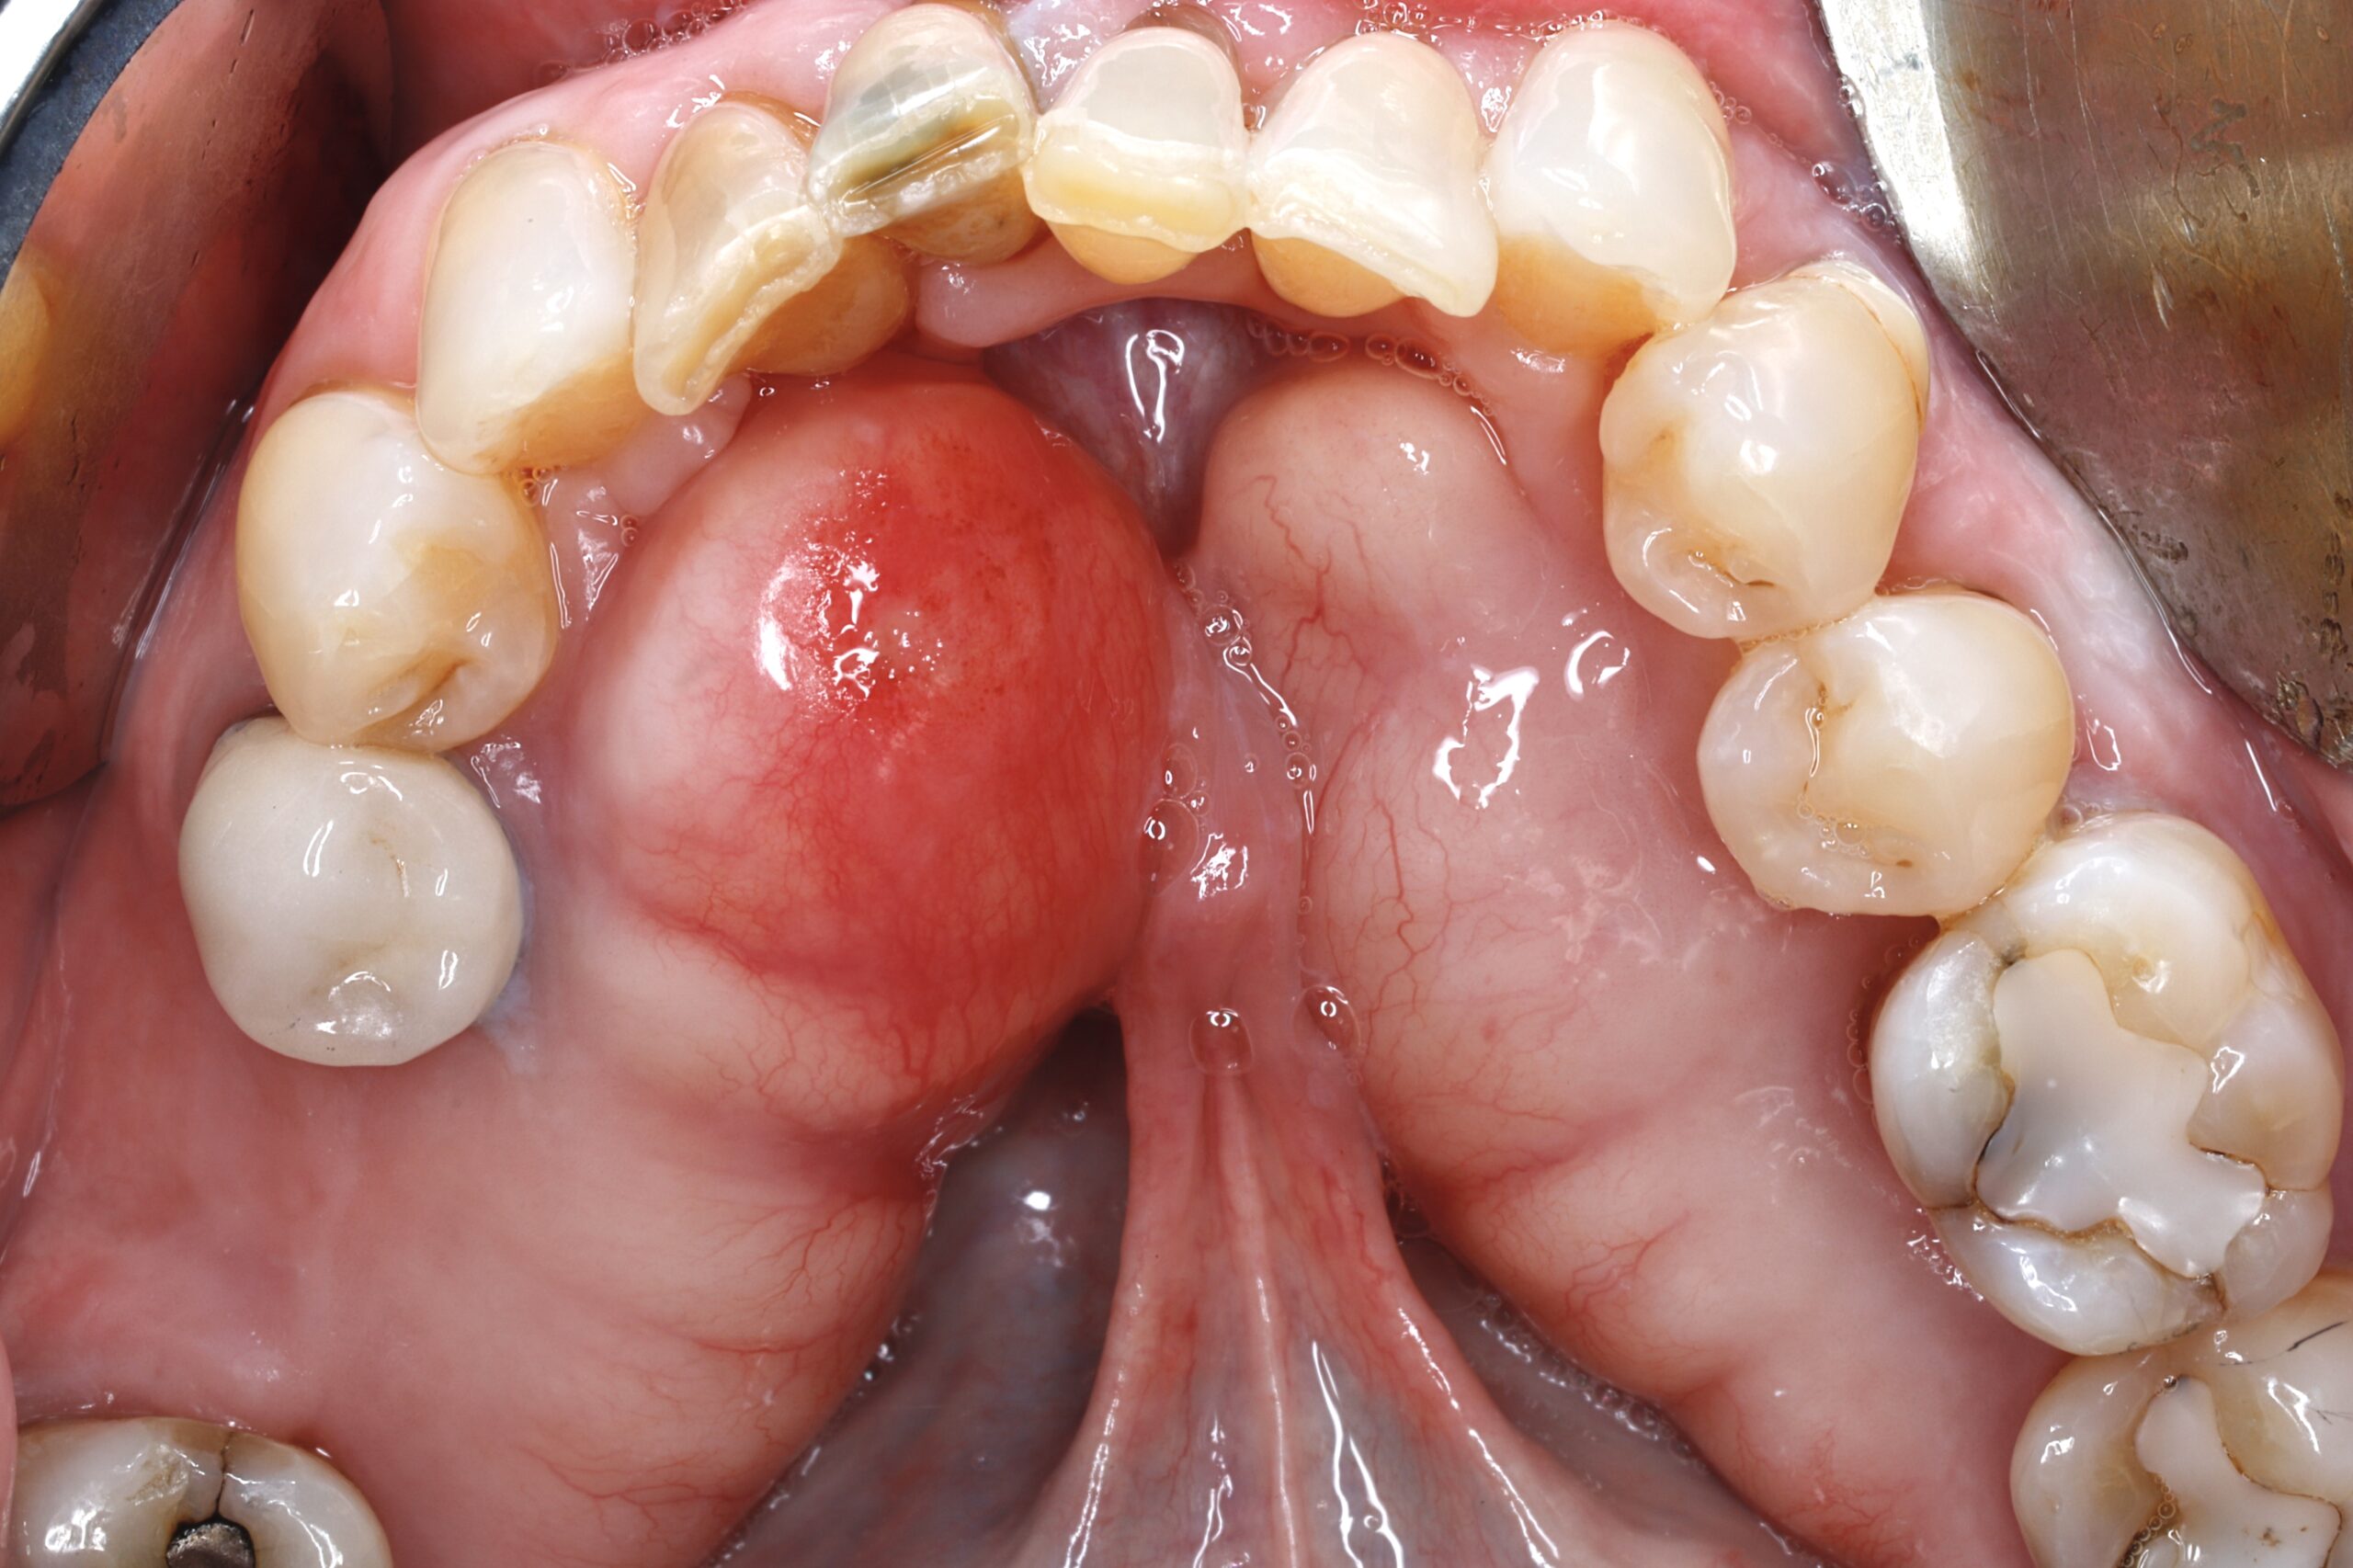

Before

After